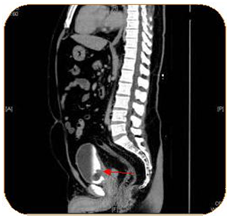

A complete blood count, liver function test, urine culture and PSA were all within normal ranges. Urine cytology revealed atypical cells. CT abdomen and pelvis with I.V contrast showed a 3.1 x 2.4 x 3 cm polypoidal mass of the trigone (Figure 1). Afterwards, the patient underwent cystoscopy which showed a solid florid mass extending from the trigone to the posterior wall of the urinary bladder, TURBT was carried out. The Histopathology slides showed cystitis cystica with cystitis glandularis (Colonic metaplasia) (Figure 2‒5).

Figure 1 A polypoidal mass and thickening of the trigone, no lymphadenopathy or metastasis could be seen.